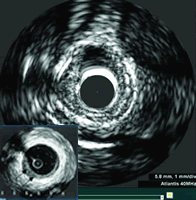

随着微型导管超声换能器和声学成像技术的飞速进步,血管内超声(intravascular ultrasound,IVUS)检查已由实验研究阶段逐步发展成为冠心病临床诊断和介入治疗中具有重要价值的新方法。IVUS利用安装在心导管顶端的微型超声换能器,在血管内发射和接收高频超声信号,实时显示血管的切面图像,能清晰显示管壁结构的厚度、管腔大小和形态等,甚至可以辨认钙化、纤维化和脂质池等病变。本文拟就IVUS的发展历程、应用现状和发展前景作一简略论述。